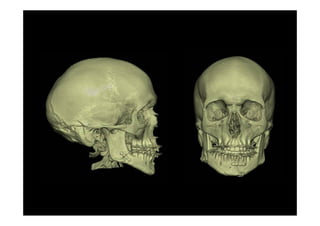

Fracturas complejas de la cara

Disyunción Cráneo Facial